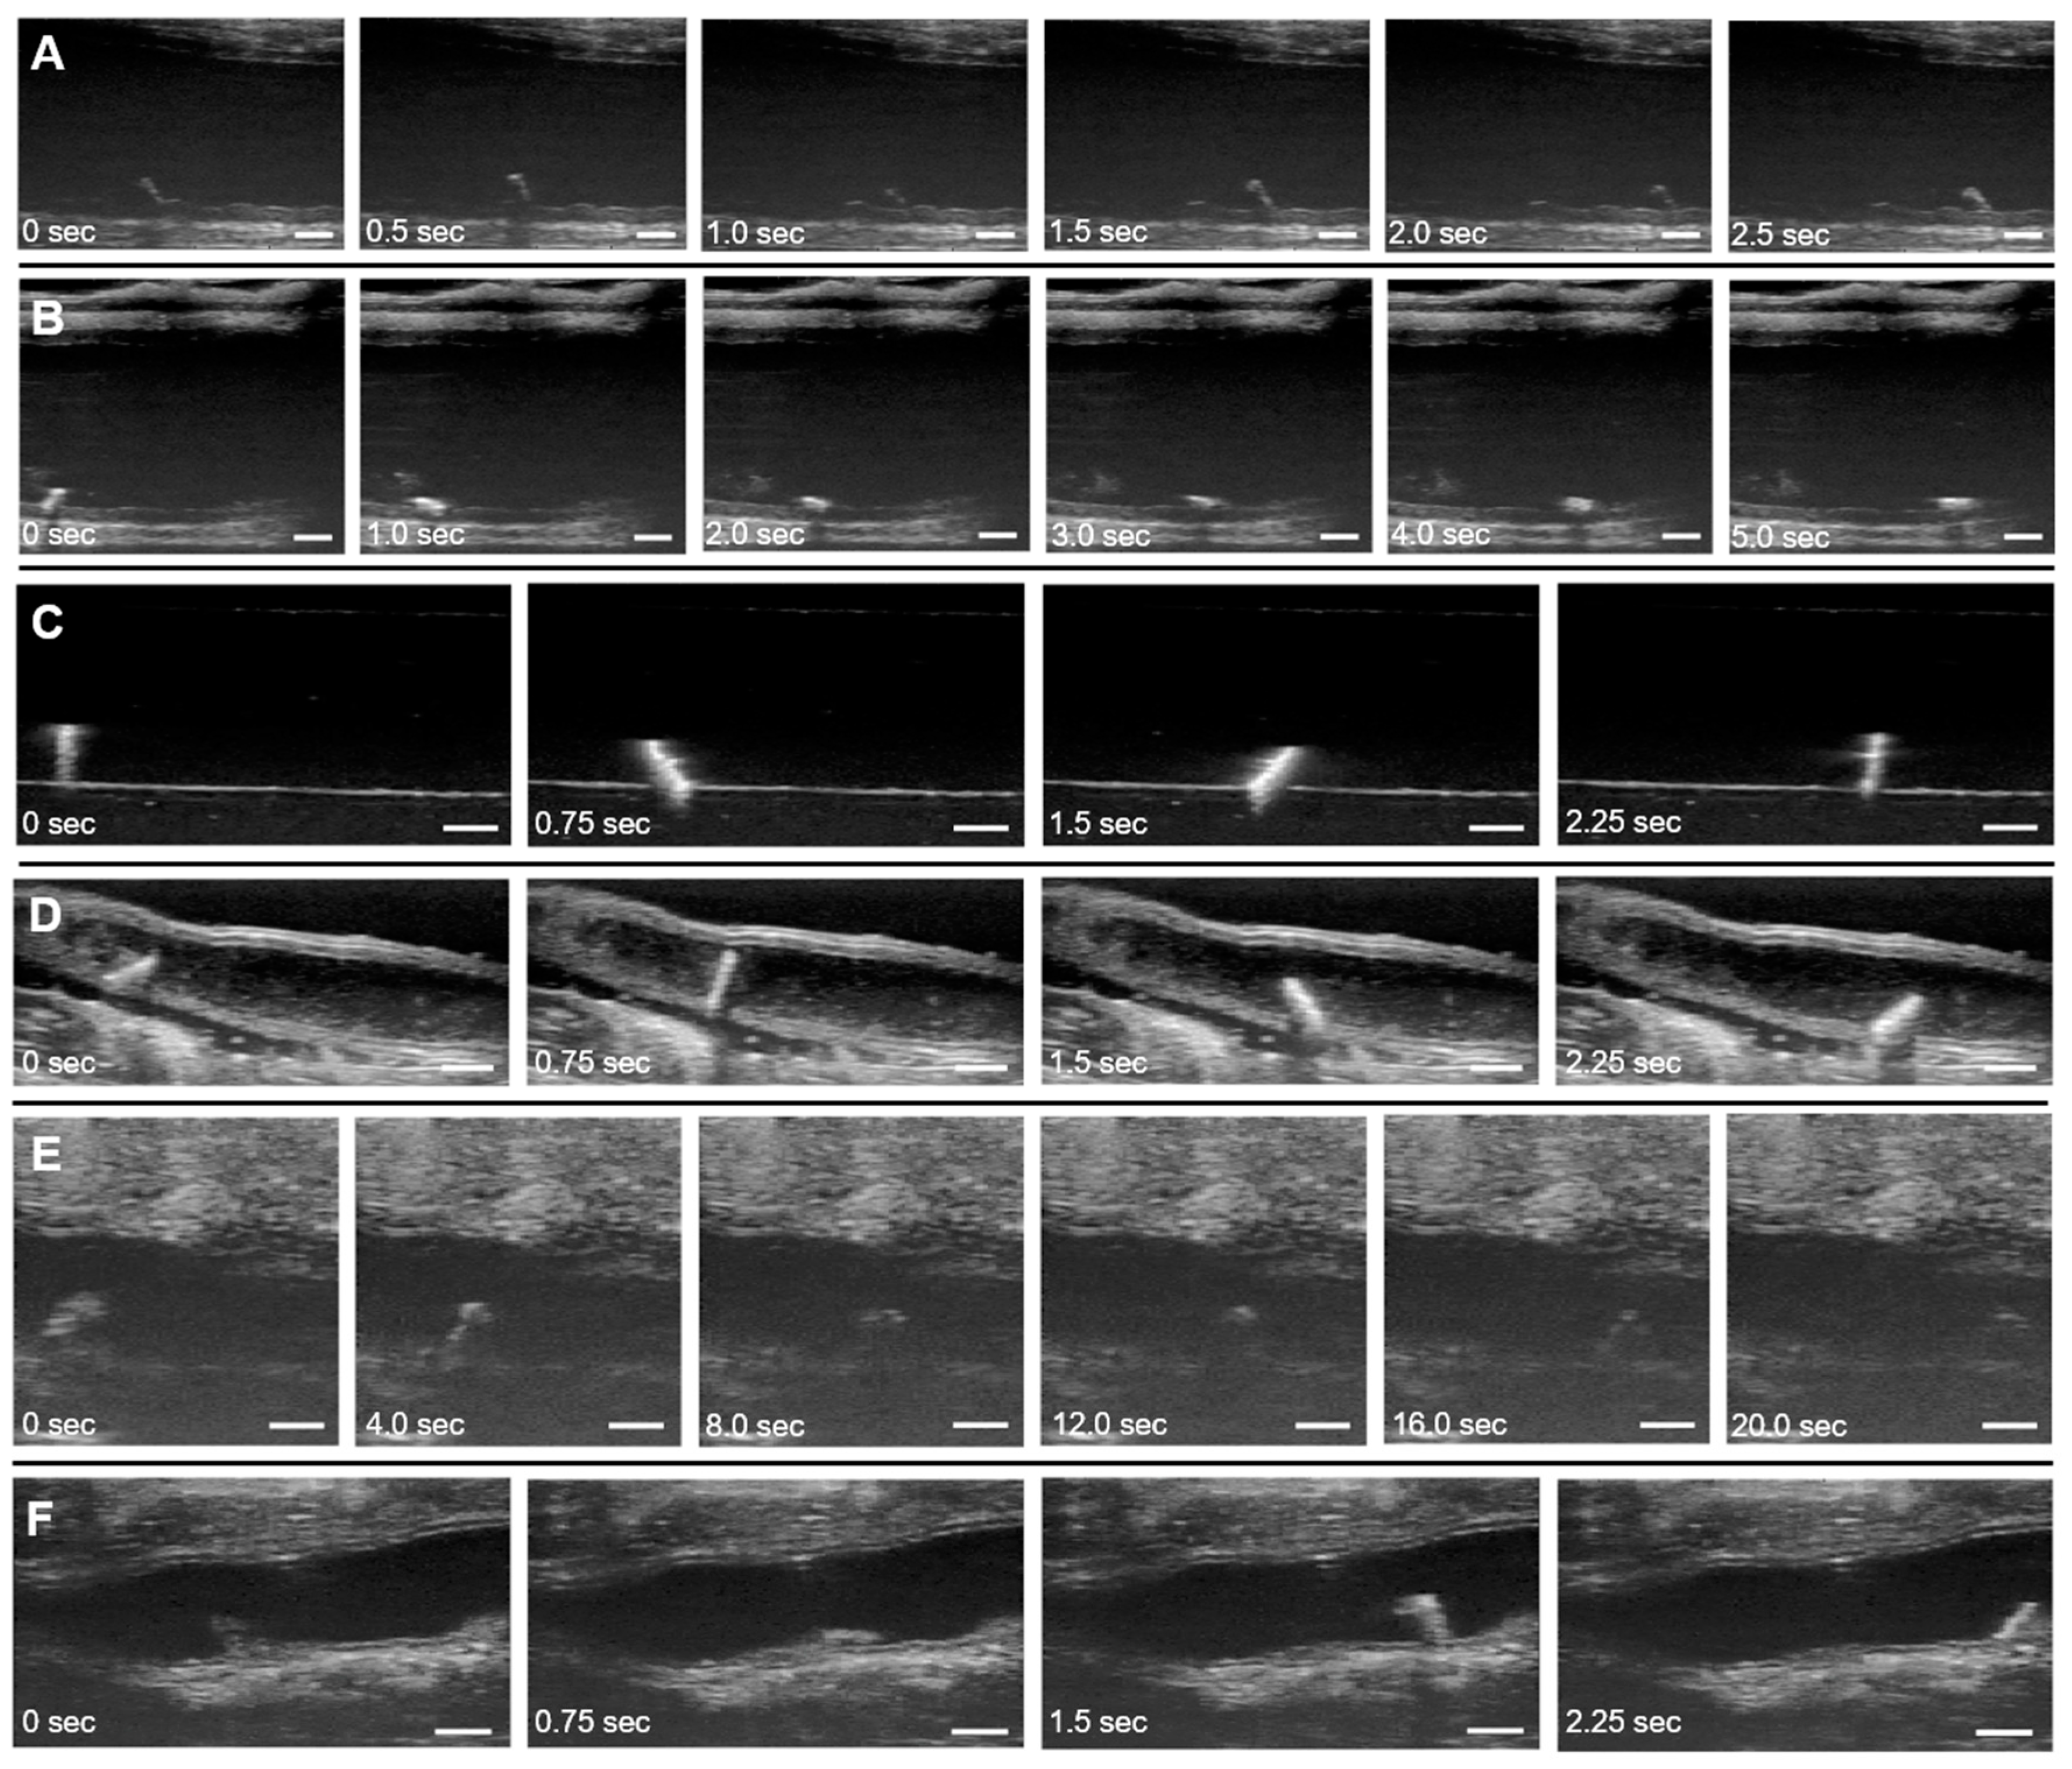

3.3.1. Ex Vivo Locomotion

3.3.2. In Vitro Locomotion

3.3.3. In Situ Dissected Locomotion

3.3.4. In Situ Intact Locomotion

3.3.5. In Vivo Locomotion